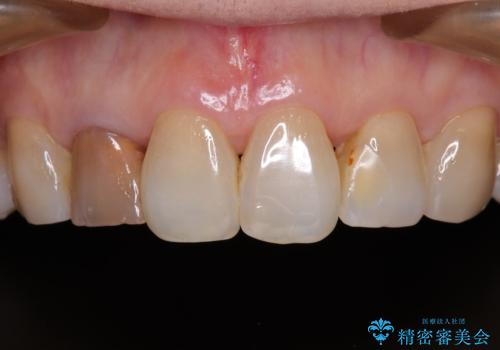

- 奥歯の目立つ銀歯と、神経が失活して変色した前歯を気にして来院された患者様です。

銀歯と歯の間に隙間があり、冷たいものがしみる知覚過敏の症状が認められたため、銀歯を白くするだけでなく、知覚過敏症状の改善も狙って補綴治療を行うこととしました。